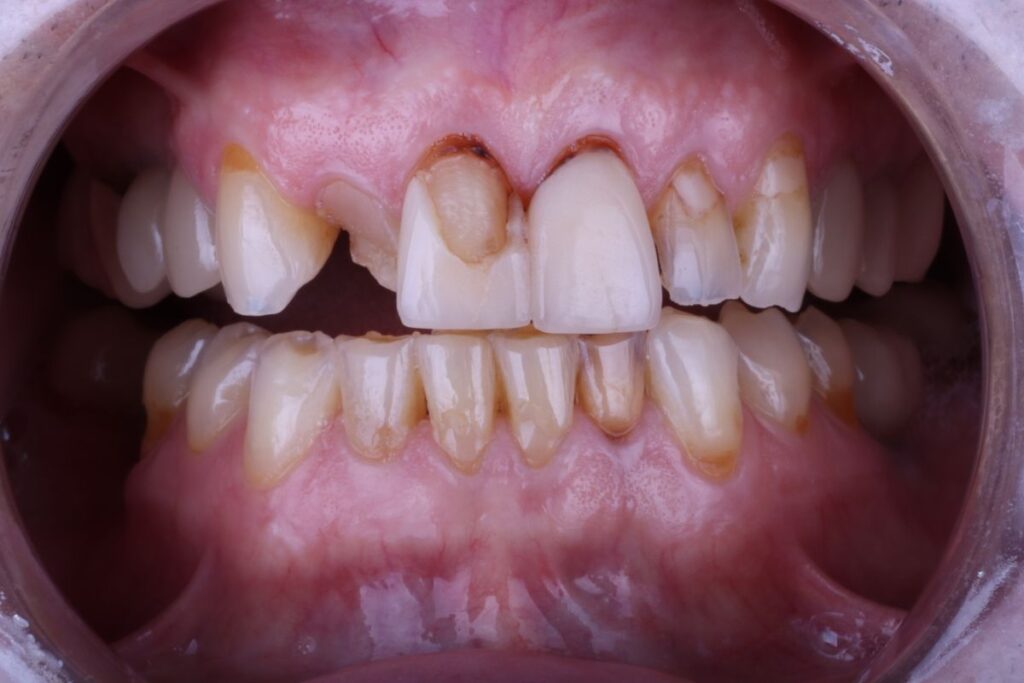

Meet Byron

Bryon came to us with significant discomfort and sensitivity in his front teeth. Teeth #7 and #8 were fractured, and teeth #7-10 had extensive decay. Bryon was in constant pain and struggled with cold sensitivity. More than the physical discomfort, his dental issues severely impacted his self-confidence. Bryon, who is naturally happy and outgoing, found himself constantly covering his mouth and hesitant to smile.

Recognizing the need for a long-term solution that would not only restore Bryon’s dental health but also enhance his smile, Dr. Perry recommended crowns. Bryon desired a brighter smile, so we opted for A1 crowns, known for their bright, white appearance and high translucency.